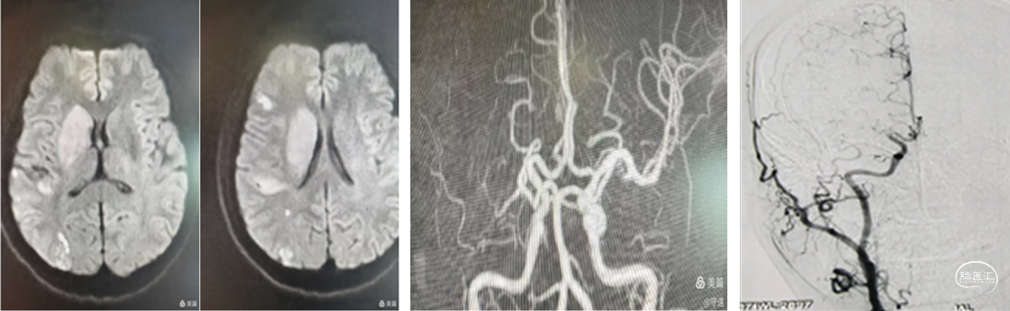

核磁显示:右侧内囊梗塞,大脑中动脉皮层段多发点状低灌注改变。MRA显示右侧大脑中动脉M1段起始部以远未显影,考虑闭塞。

脑血管造影显示:M1起始部以远末显影,大脑前和大脑后动脉通过软膜动脉代偿。

结合影像评估考虑ICAS病变可能性大。

再次球囊扩张:再次将球囊扩张导管置于M1段,在6个大气压(命名压)下扩张导管,泄压后回撤导管造影,右侧大脑中动脉全程血流通畅达3级,远端未见明确血栓逃逸。M1段毛糙,考虑残余狭窄约40%。术中推注替罗非班10mL,撤出导管系统造影大脑中动脉全程血流通畅。

术后24小时复查CT:右侧內囊梗塞区浅淡高密度影,考虑内囊为终末血管,再灌注渗出。